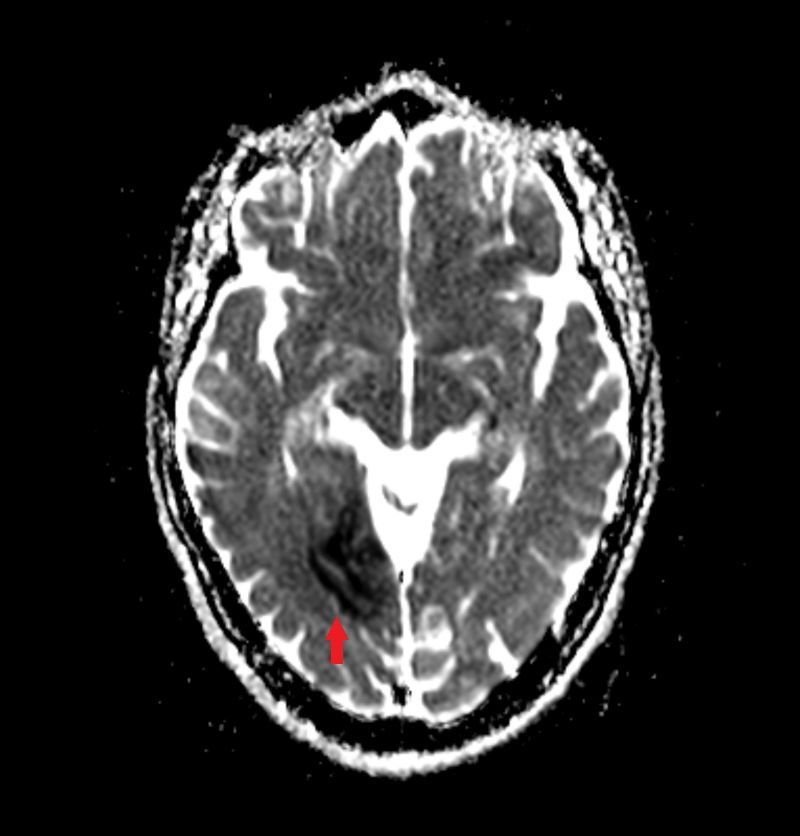

diffusionsgewichetes Bild bei Infarkt

gleicher Patient mit ADC-Karte